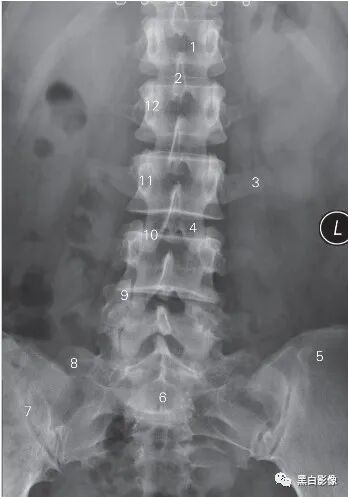

图6-4 腰椎正位DR平片

1 第1腰椎椎体 1st lumbar vertebral body

2 棘突 spinous process 3 横突 transverse process

4 L3/4椎间隙 L3/4 lumber intervertebrale space

5 髂骨 ilium 6 骶骨 sacrum

7 骶髂关节 sacroiliac joint 8 骶骨翼 sacral wing

9 上关节突 superior articular process

10 下关节突 inferior articular process 11 椎弓根 vertebral pedicle

12 关节突关节 zygapophyseal joint